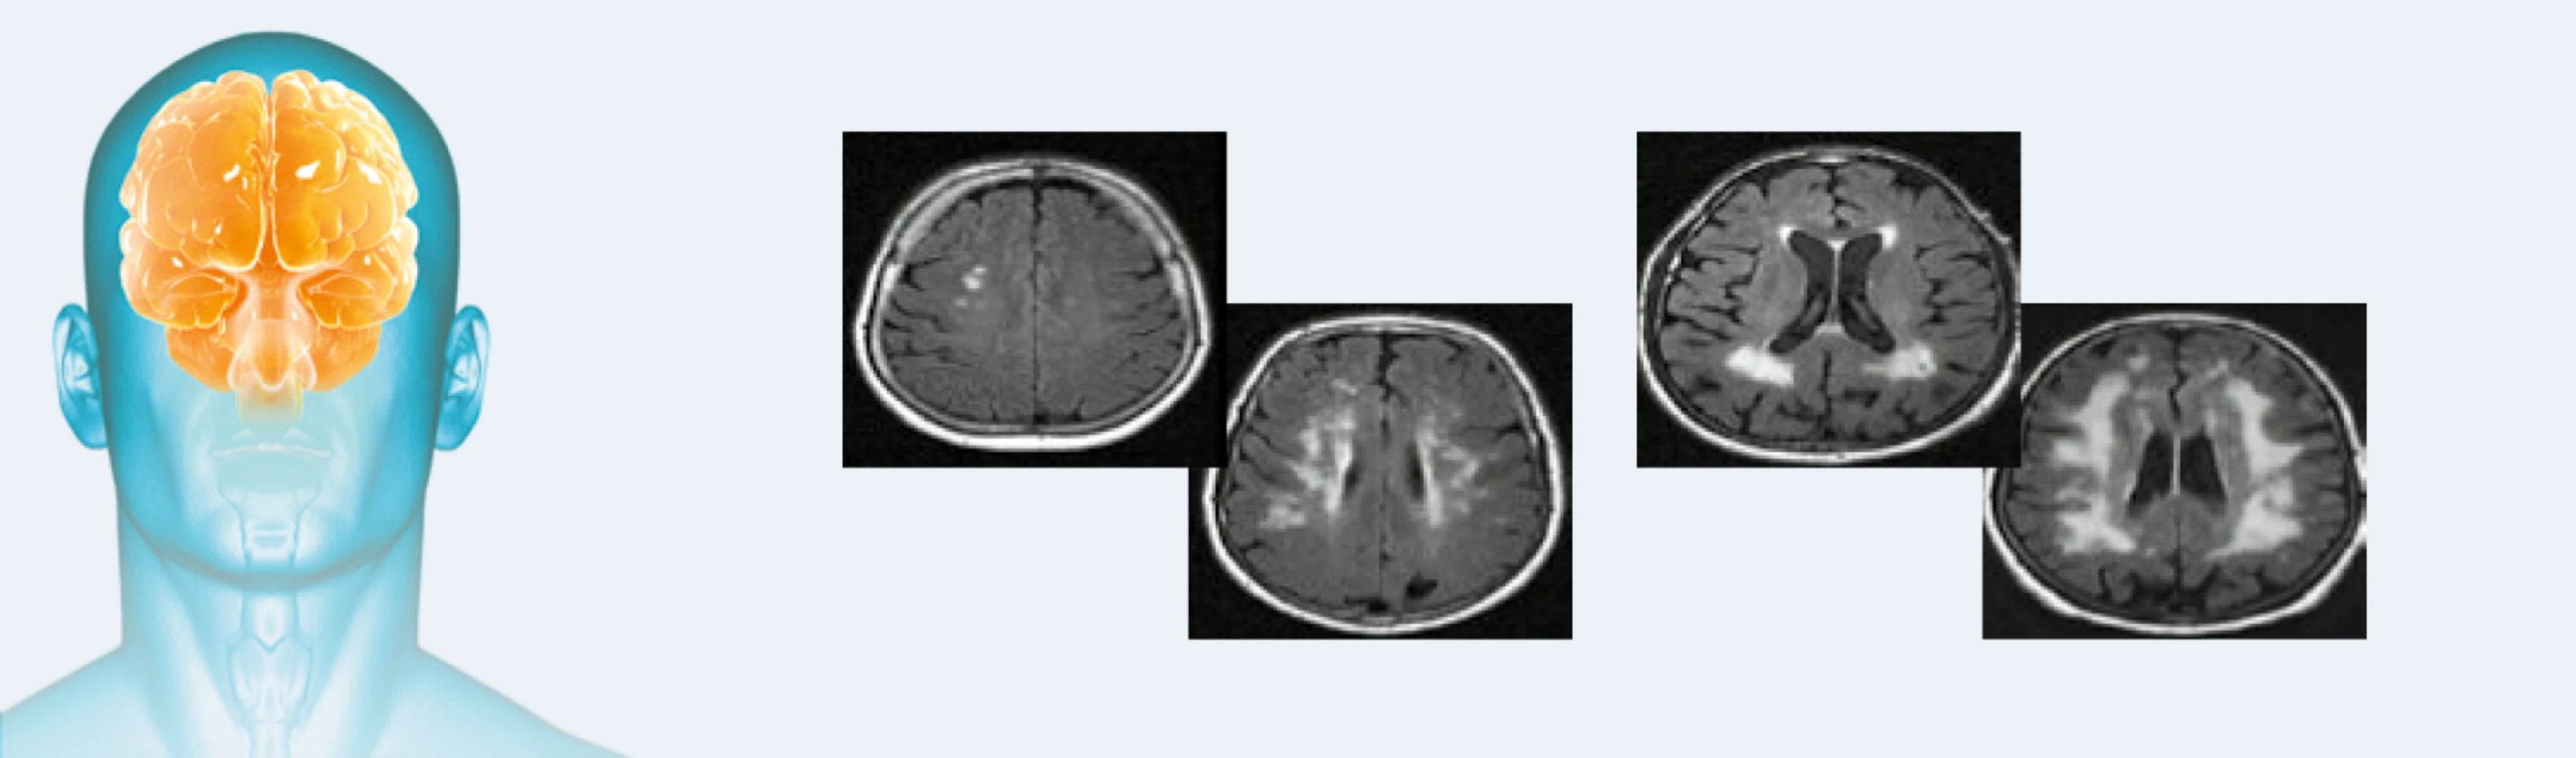

Morbus Fabry – Factsheet für Neurologen

Neurologische Symptome gehören zu den frühesten und häufigsten Symptomen des Morbus Fabry. Das Factsheet Morbus Fabry in der Neurologie enthält die typischen neurologischen Befunde bei Morbus Fabry und führt die wesentlichen Eingangsuntersuchungen auf. Zudem erhält er Informationen über den FabryScan, ein digitaler Fragebogen, um Patient:innen mit chronischen Schmerzen unklarer Ursache auf das Vorliegen der Erkrankung Morbus Fabry schneller zu erkennen.